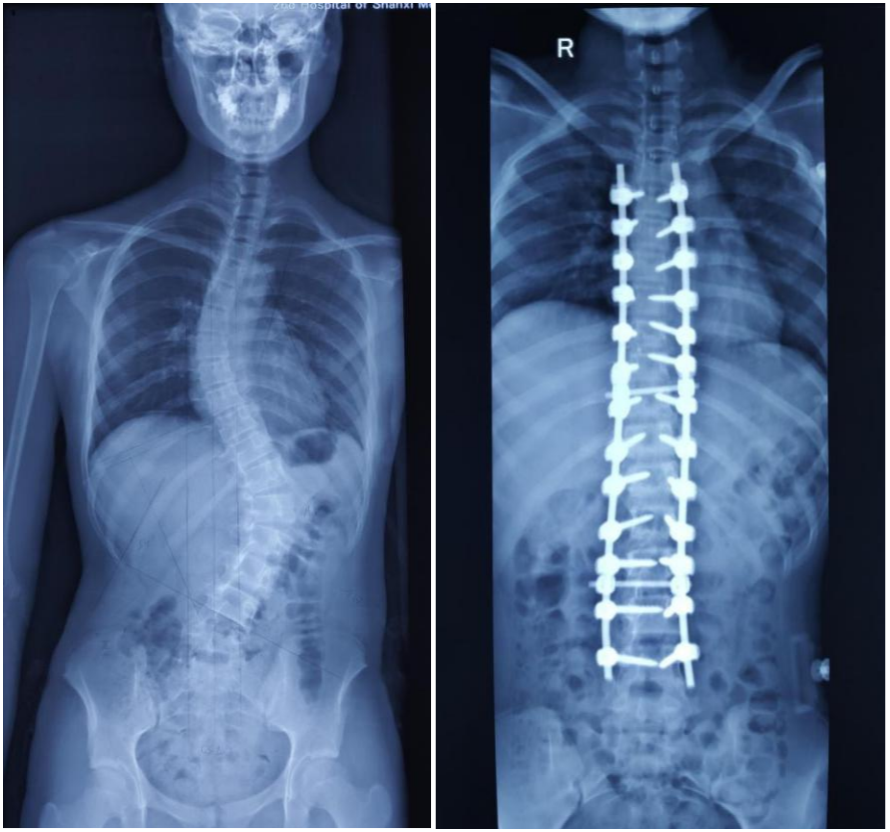

这位家长听说太原市中心医院骨科汾东二病区是脊柱微创治疗优秀学科,慕名来诊。小患者入院后,骨科汾东二病区脊柱团队专家对患者详细查体,积极完善影像学资料,在科主任陈剑锐和外聘专家杨晋才教授(北京朝阳医院骨科专家)的指导下讨论、分析,精心制定手术方案,在全麻下为患者进行“特发性脊柱侧弯后路矫形椎弓根钉内固定术”手术。

手术历时4小时,在手术团队、麻醉手术科医生的共同努力下,小患者脊柱侧弯畸形达到矫正变直,手术效果非常理想。经过术后的康复训练,她已逐渐开始下床活动,在支具保护下已可自如行走。2个月的康复后,小患者可如期正常进入高中的学习生活。

(术前术后影像对比)